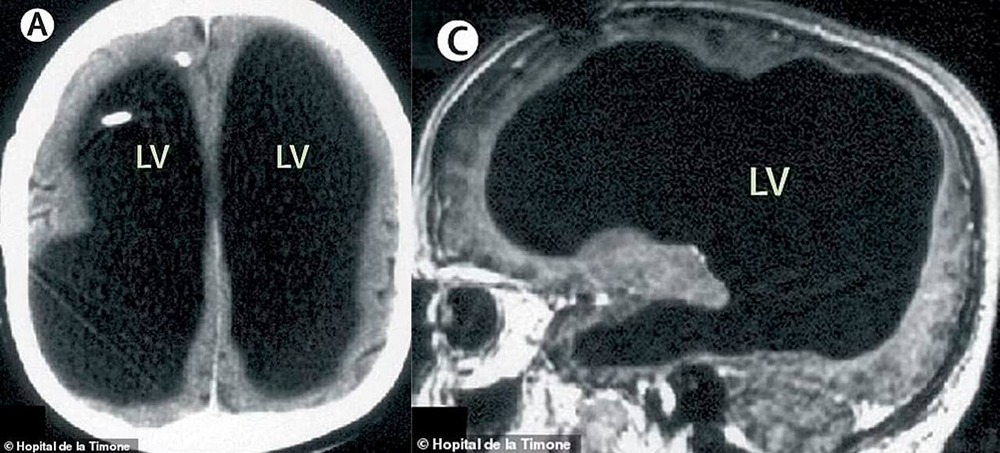

В возрасте 44 лет француз узнал, что его мозг практически полностью отсутствует. Это стало для него полной неожиданностью. Всё началось с лёгко...